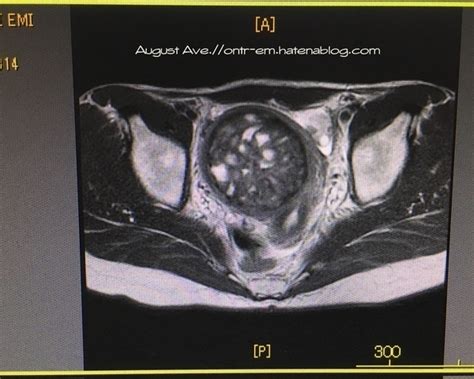

UEA治療前の子宮筋腫9cmのMRI画像を紹介 - August Ave.

UEA治療前の子宮筋腫9cmのMRI画像を紹介 - August Ave. from cdn-ak.f.st-hatena.com